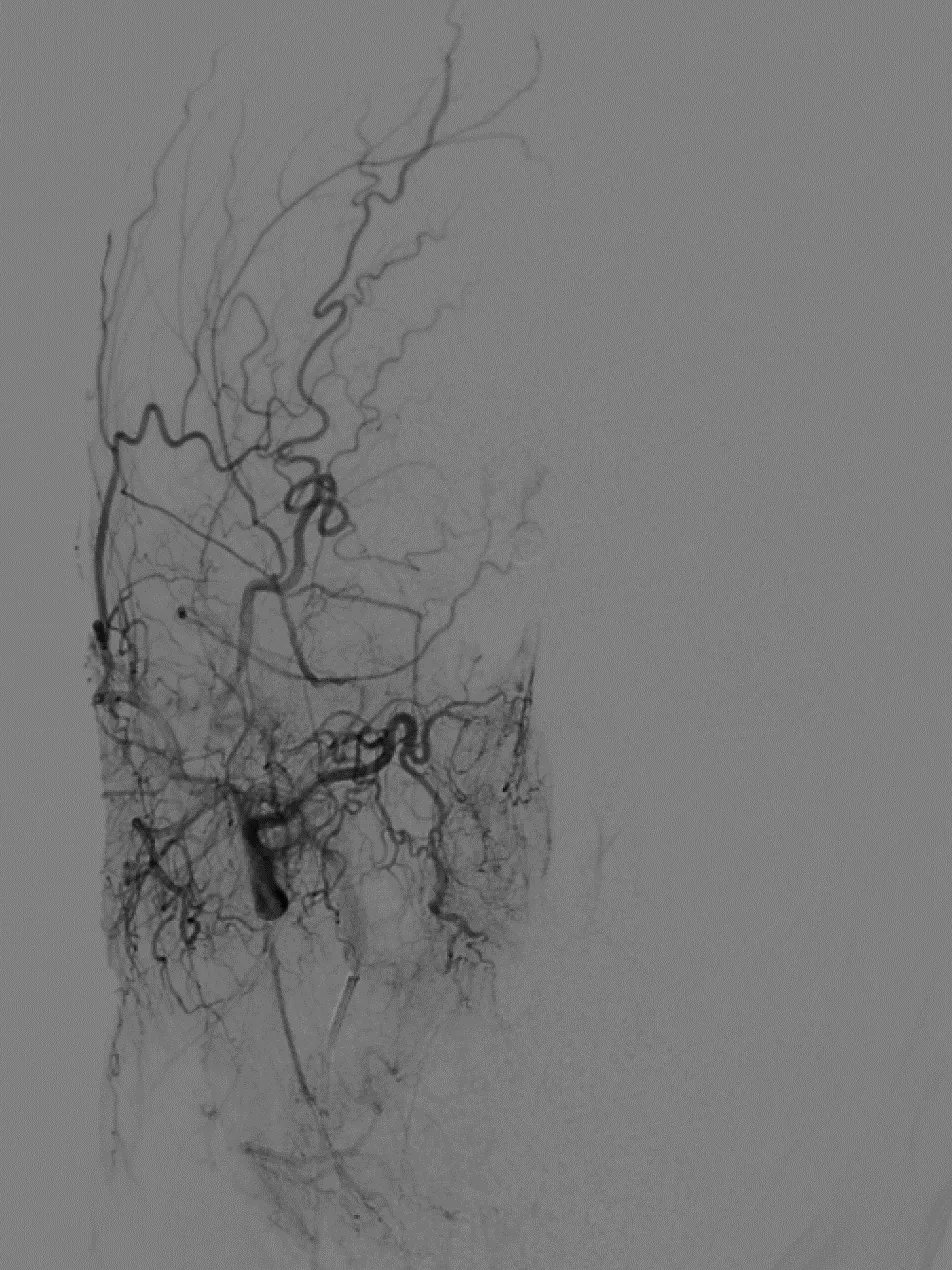

术前造影

左颈总造影,未见异常供血

右颈外造影,可见右侧蝶腭动脉分支供血,但无良好路径显示

右颈内造影,可见右侧眼动脉-筛后动脉供血,见经额底静脉-双侧额部皮层静脉向上矢状窦方向引流

经右眼动脉工作路径

SONIC微导管到位后,手推造影确认

SONIC微导管造影证实

首次注胶

首次注胶后造影仍见瘘口区显影

继续注胶,见部分反流,停顿

停顿等待后继续注胶

造影显示瘘口消失

拔管过程,见SONIC微导管头端解脱

拔管后造影:

SONIC微导管头端解脱,右侧眼动脉显影良好,未见拔管牵拉痉挛表现

可见SONIC微导管可解脱头端显影